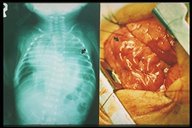

After completion of the plication of diaphragm, the diaphragm is strengthened and flattened

After completion of the plication of diaphragm, the diaphragm is strengthened and flattened flattened (right) and chest X-ray showed that the affected diaphragm was at the normal level.